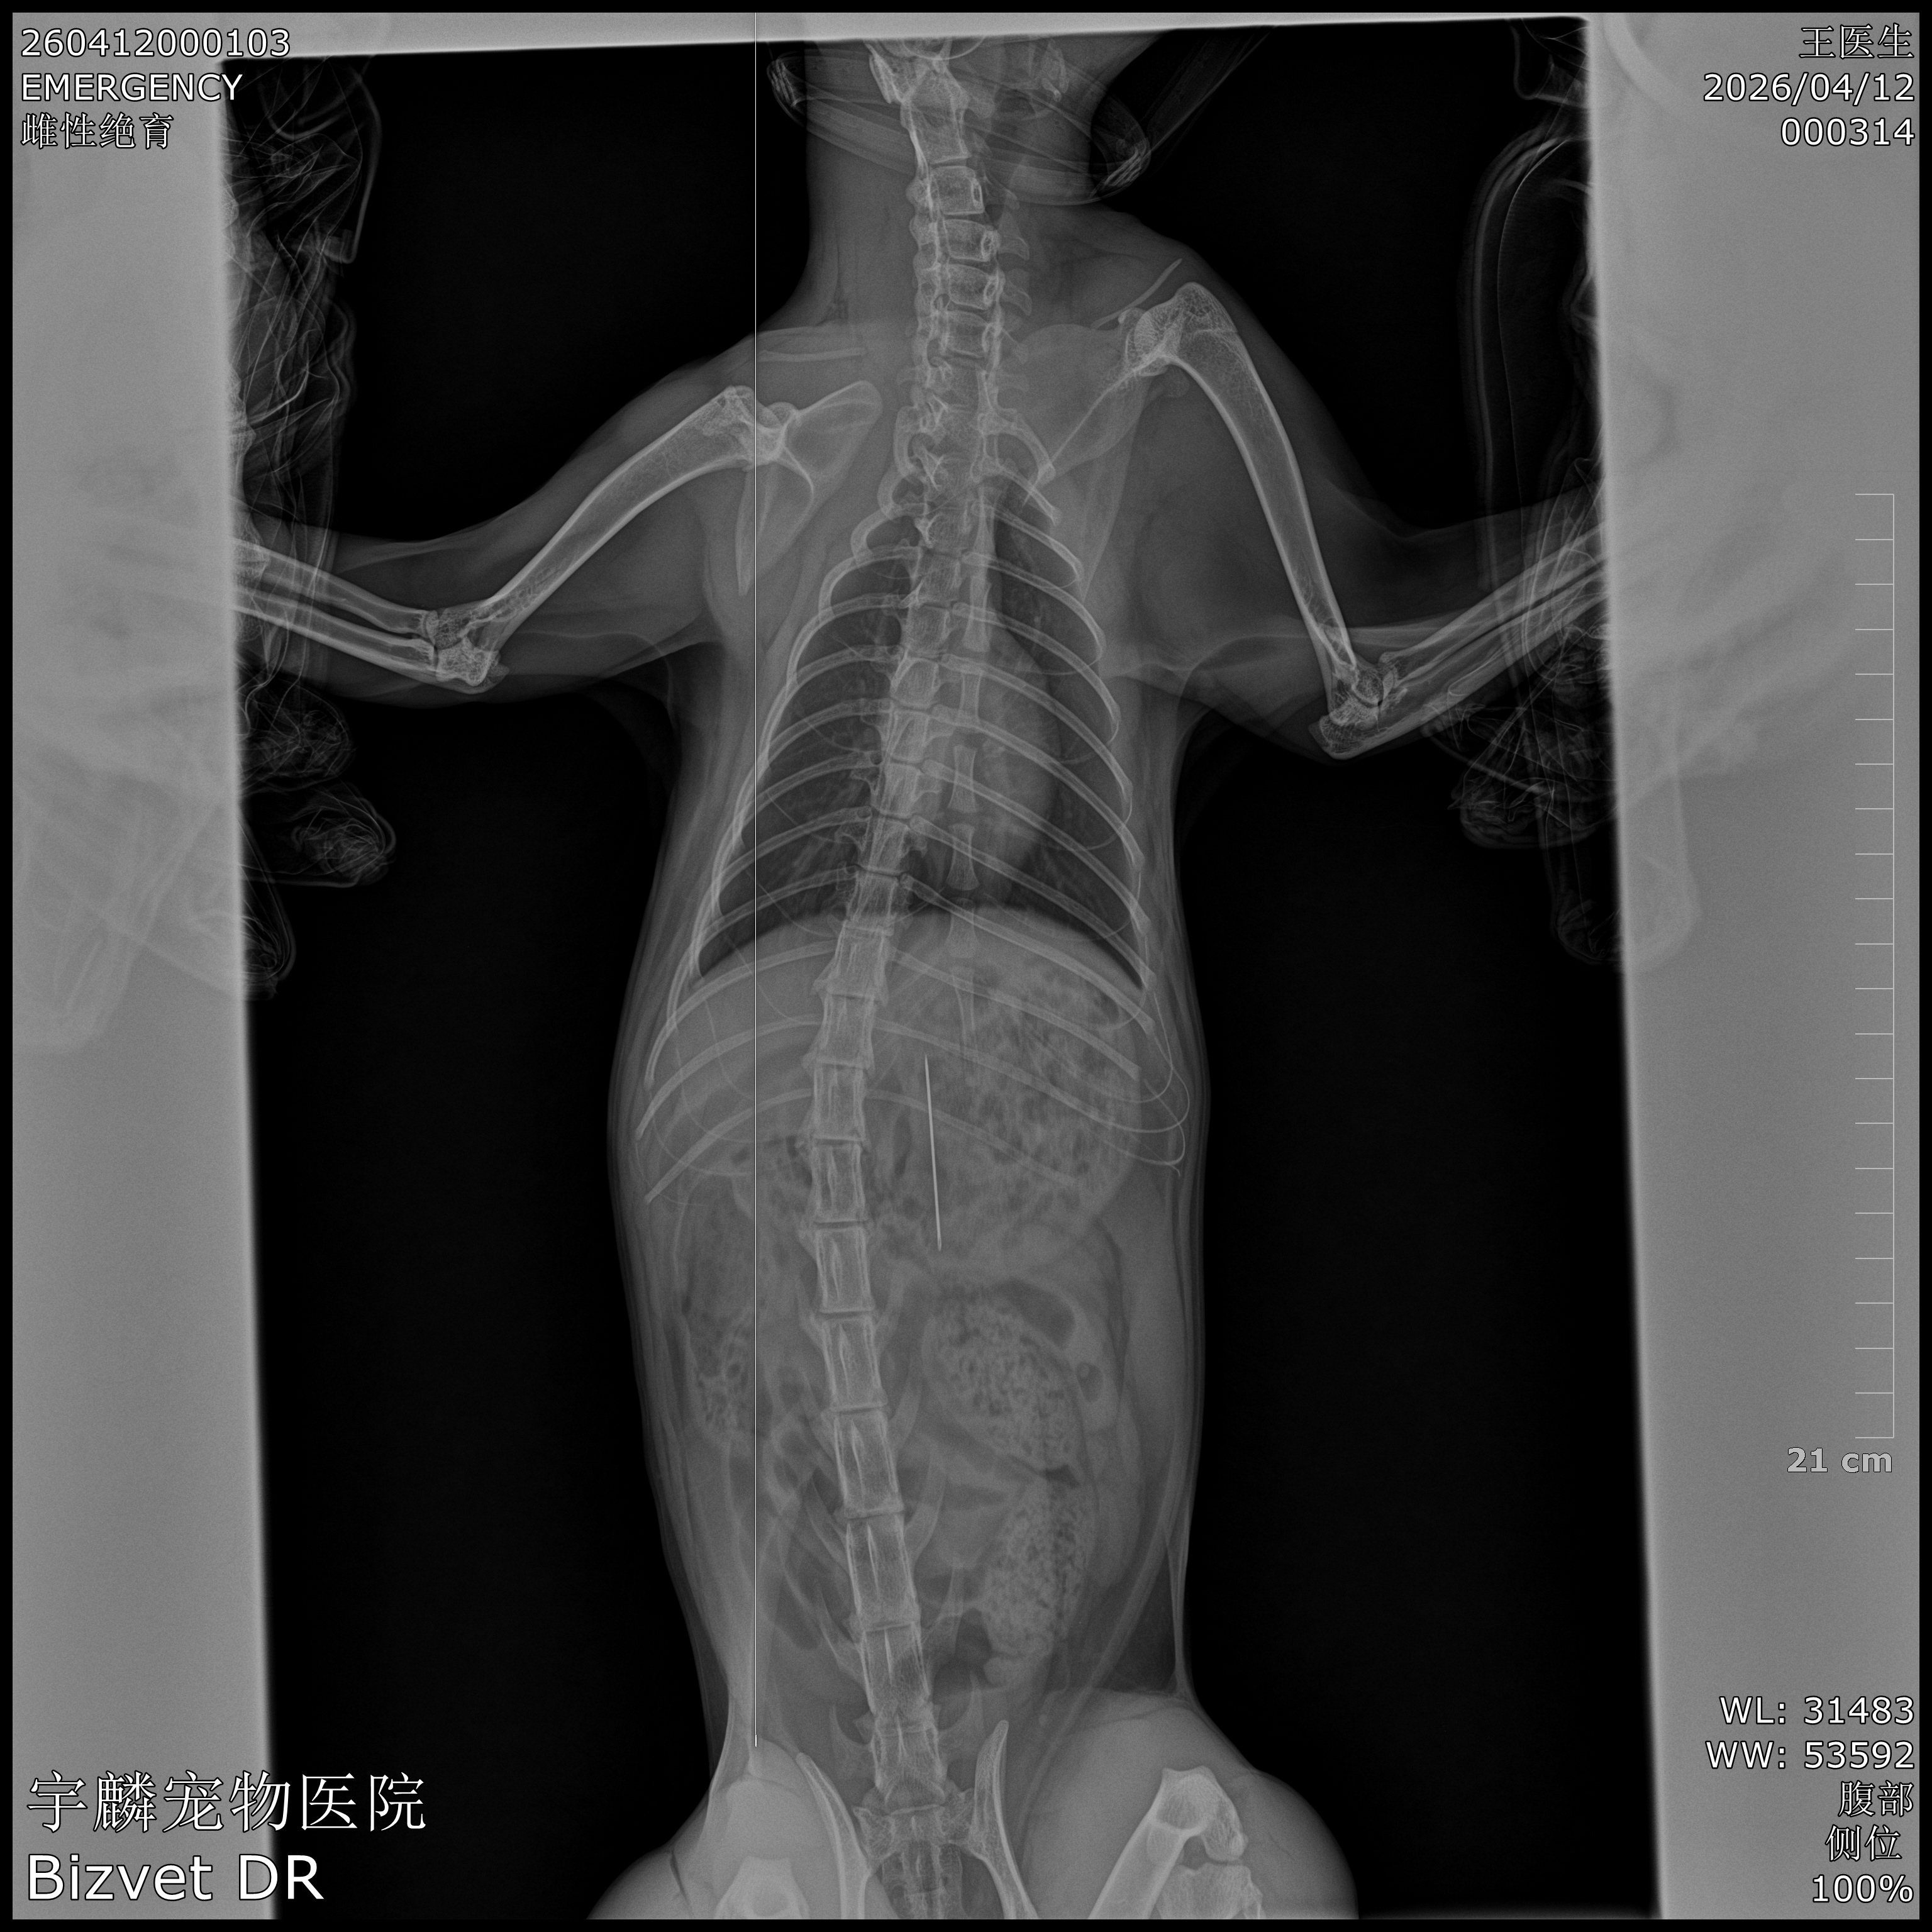

凌晨1点的生死营救:一枚钢针的“食道逆行”奇迹2026年4月12日凌晨1点,城市已沉入梦乡,携宠宇麟宠物医院的灯却为一只名叫“元宝”的猫咪骤然亮起。元宝趁主人不备,吞下了一枚尖锐的缝衣针。X光片上,那枚针静静躺在胃里,像一颗随时会引爆的定时炸弹——尖锐的针尖随时可能刺穿胃壁,游走进腹腔,造成致命的腹...